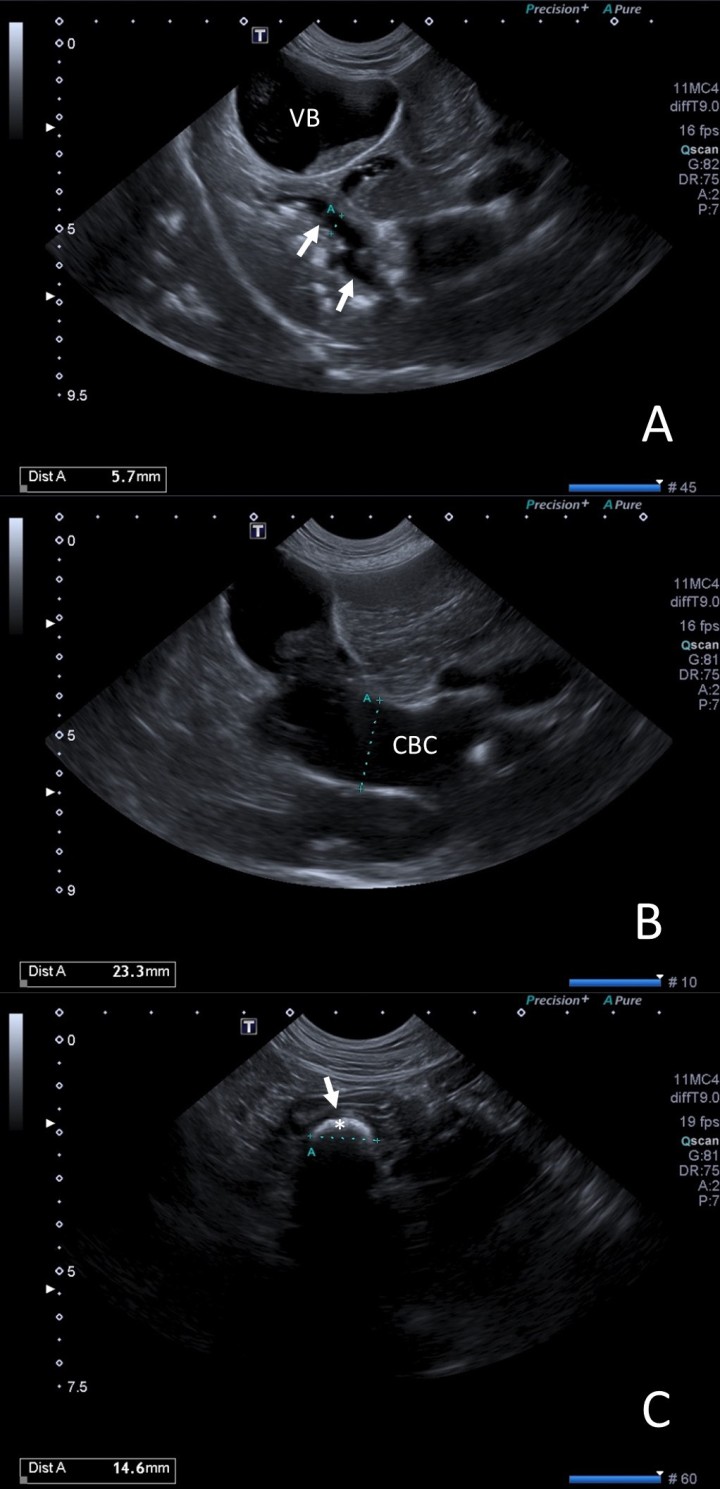

Para localizar y caracterizar dichas estructuras radiopacas detectadas, así como valorar el hígado y las vías biliares se llevó a cabo una ecografía abdominal (Fig. 2). El estudio ecográfico reveló un parénquima hepático hiperecogénico con bordes redondeados. Las vías biliares intrahepáticas estaban dilatadas con abundante sedimento y múltiples pequeñas estructuras hiperecoicas que generaban sombra acústica. La vesícula biliar se encontraba distendida con moderada cantidad de sedimento biliar, pero sin colelitos visibles en su interior en el momento del estudio (Fig. 2A). La pared de la vesícula biliar (VB) presentó un leve aumento en su espesor (3 mm). El conducto biliar común (CBC) se encontraba marcadamente distendido (23 mm) en toda su longitud (Fig. 2B) hasta alcanzar una estructura hiperecoica de 14 mm x 9 mm con sombra acústica que obstruía completamente la luz del colédoco; dicha estructura se encontraba inmediatamente craneal a la papila duodenal (Fig. 2C).

<p>(<strong>A</strong>) Se observa la vesícula biliar (VB) distendida con contenido en su interior, así como dilatación de las vías biliares intrahepáticas (flechas) con pequeñas estructuras hiperecogénicas que causan sombra acústica. (<strong>B</strong>) Conducto biliar común (CBC) marcadamente distendido. (<strong>C</strong>) Conducto biliar común a su llegada a la papila duodenal (flecha), donde se observa una estructura hiperecoica (*) de gran tamaño responsable de la obstrucción.</p>

(A) Se observa la vesícula biliar (VB) distendida con contenido en su interior, así como dilatación de las vías biliares intrahepáticas (flechas) con pequeñas estructuras hiperecogénicas que causan sombra acústica. (B) Conducto biliar común (CBC) marcadamente distendido. (C) Conducto biliar común a su llegada a la papila duodenal (flecha), donde se observa una estructura hiperecoica (*) de gran tamaño responsable de la obstrucción.